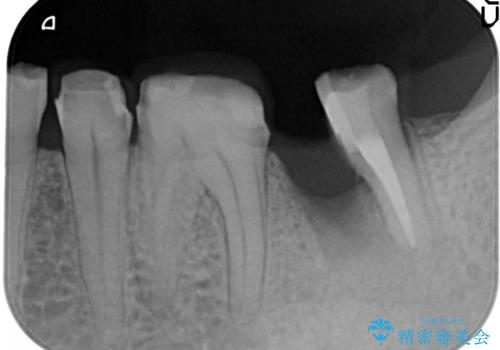

近心根が垂直破折しており保存不可能で抜歯適応だと判断しましたが、できることなら少しでも保存したいとの希望があり、今後のリスクを説明した上で遠心根を保存する意思決定を行いました。

今回の症例は遠心根を保存するメリット・デメリットを患者さんと話し合い、治療を進めております。